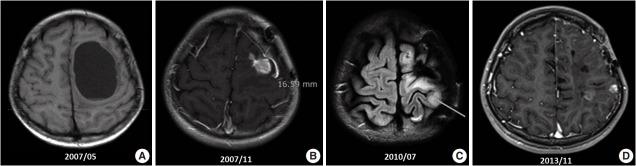

Ependymoma is the third most common pediatric primary brain tumor. Ependymomas are categorized according to their locations and genetic abnormalities, and these two parameters are important prognostic factors for patient outcome. For supratentorial (ST) ependymomas, RELA fusion-positive ependymomas show a more aggressive behavior than YAP1 fusion-positive ependymomas. Extracranial metastases of intra-axial neuroepithelial tumors are extremely rare. In this paper, we report a case of aggressive anaplastic ependymoma arising in the right frontoparietal lobe, which had genetically 1q25 gain, CDKN2A homozygous deletion, and L1CAM overexpression. The patient was a 10-year-old boy who underwent four times of tumor removal and seven times of gamma knife surgery. Metastatic loci were scalp and temporalis muscle overlying primary operation site, lung, liver, buttock, bone, and mediastinal lymph nodes. He had the malignancy for 10 years and died. This tumor is a representative case of RELA fusion-positive ST ependymoma, showing aggressive behavior.

室管膜瘤是第三常见的小儿原发性脑肿瘤。室管膜瘤根据其位置和基因异常进行分类,这两个参数是患者预后的重要预测因素。对于幕上(ST)室管膜瘤,RELA融合阳性的室管膜瘤比YAP1融合阳性的室管膜瘤表现出更具侵袭性的行为。轴内神经上皮肿瘤的颅外转移极为罕见。在本文中,我们报告了一例发生在右额顶叶的侵袭性间变性室管膜瘤病例,该肿瘤在基因上存在1q25增益、CDKN2A纯合缺失和L1CAM过表达。患者为一名10岁男孩,接受了4次肿瘤切除术和7次伽玛刀手术。转移部位为头皮和原发手术部位上方的颞肌、肺、肝、臀部、骨和纵隔淋巴结。他患恶性肿瘤10年后死亡。该肿瘤是RELA融合阳性ST室管膜瘤的典型病例,表现出侵袭性行为。